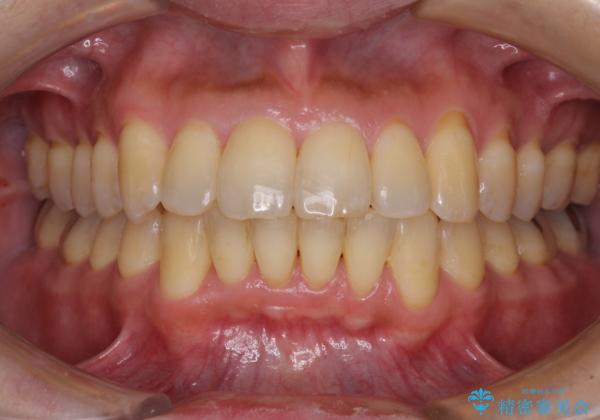

前歯のデコボコ ワイヤー装置での短期間治療

- 前歯のデコボコを気にして来院された患者様です。

インビザラインまたはワイヤー装置、どちらでも対応可能でしたが、自己管理の少なさ、期間の短さから、ワイヤー装置による矯正治療を行うこととしました。

治療開始の頃は、食事や歯磨きが慣れず、装置が頻繁に脱落しましたが、2,3ヶ月ほどで慣れ、その後は1年ほどで治療を終えることができました。